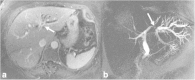

Malignancies of the biliary tract include cholangiocarcinoma, gallbladder cancers and carcinoma of the ampulla of Vater. Biliary tract adenocarcinomas are the second most common primary hepatobiliary cancer. Due to their slow growing nature, non-specific and late symptomatology, these malignancies are often diagnosed in advanced stages with poor prognosis. Apart from incidental discovery of gall bladder carcinoma upon cholecystectomy, early stage biliary tract cancers are now detected with computed tomography (CT) and magnetic resonance imaging (MRI) with magnetic resonance cholangiopancreatography (MRCP). Accurate characterization and staging of these indolent cancers will determine outcome as majority of the patients' are inoperable at the time of presentation. Ultrasound is useful for initial evaluation of the biliary tract and gallbladder masses and in determining the next suitable modality for further evaluation. Multimodality imaging plays an integral role in the management of the biliary tract malignancies. The imaging techniques most useful are MRI with MRCP, endoscopic retrograde cholangiopancreatography (ERCP), endoscopic ultrasound (EUS) and positron emission tomography (PET). In this review we will discuss epidemiology and the role of imaging in detection, characterization and management of the biliary tract malignancies under the three broad categories of cholangiocarcinomas (intra- and extrahepatic), gallbladder cancers and ampullary carcinomas.